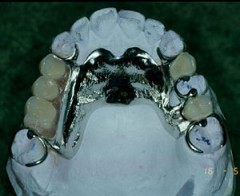

Protesi Sociale

I pazienti parzialmente o completamente edentuli presentano importanti deficit masticatori , fonatori ed estetici .

Presso le nostre sedi è possibile trattare tali casi attraverso l'installazione di protesi rimovibili che ripristinino le arcate dentarie consentendo al soggetto una corretta funzione masticatoria ed una normale vita di relazione.

Nei casi in cui il paziente abbia subìto , per motivi oncologici o chirurgici in generale , una massiva demolizione delle strutture mascellari è disponibile un servizio dedicato di terapia implantoprotesica allo scopo di ristabilire le adeguate funzioni cui il cavo orale è predisposto cercando di limitare il piu' possibile i deficit sopraggiunti.

![]() | ![]() |